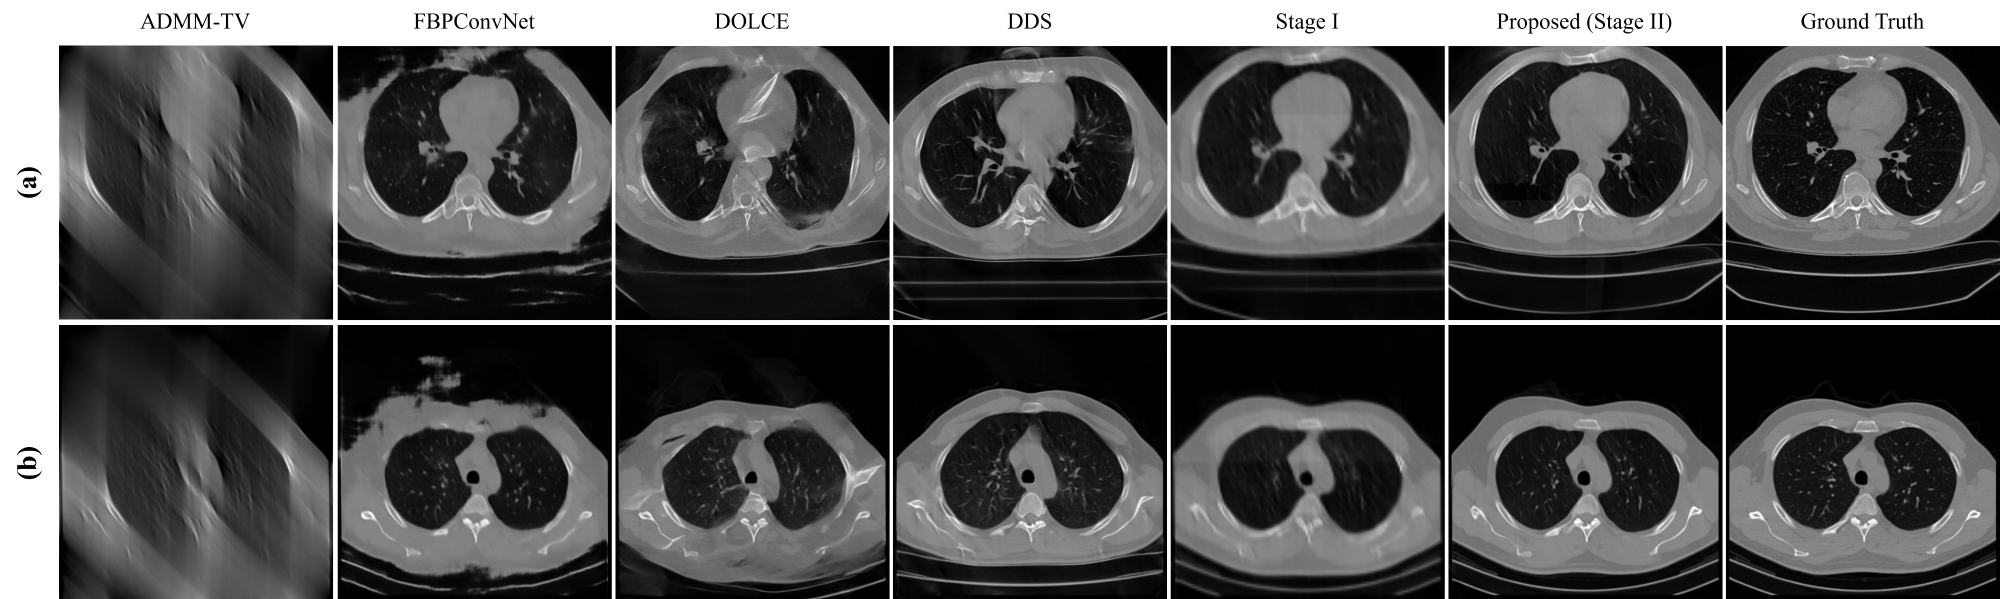

Fig. 4 presents qualitative comparisons of reconstructions via different methods across 120°, 90°, and 60° LACT setting. Each column depicts reconstructions via different methods, with magnified patches highlighting anatomical differences.

For 120° data acquisition, all deep learning methods are capable of recovering fine structures. Supervised learning methods such as FBPConvNet and DOLCE exhibit local details close to the reference, especially in multiple rounded soft-tissues marked by red boxes in Fig.4 (a). Although the unsupervised DDS model yields sharper edges and bone contrast, it introduces artifacts in soft tissue areas, which potentially affect diagnosis. Our method achieves soft-tissue recovery comparable to DOLCE, and artifact suppression better than other methods, suggesting benefits of metadata guidance in integrating data fidelity of supervised learning with global distribution modeling of unsupervised approaches.

As the angle narrows, the advantage of semantic guidance becomes more pronounced. In a case of bone structure recovery at 90°, only the proposed method reconstructs bone patterns visibly consistent with the ground truth (Fig.4 (b)). When the angle further decreases to 60°, the recovery of low-contrast soft tissues becomes significantly more challenging. As shown in Fig.4 (c), FBPConvNet produces blurry soft tissue regions with severely diminished contrast. Diffusion-based methods partially alleviate this issue, but still lose structural consistencies. Our method produces the most faithful reconstructions, with minimal artifacts and well-preserved details. Similar trends are observed in cardiac images in Fig.4 (d).

Beyond comparisons with reconstruction methods, Figs.4, 5, and 6 include intermediate results from Stage I of our framework. Although these initial reconstructions appear relatively blurry, they already exhibit reduced limited-angle artifacts compared to FBPConvNet, demonstrating the effectiveness of metadata-driven priors in guiding early-stage reconstructions.